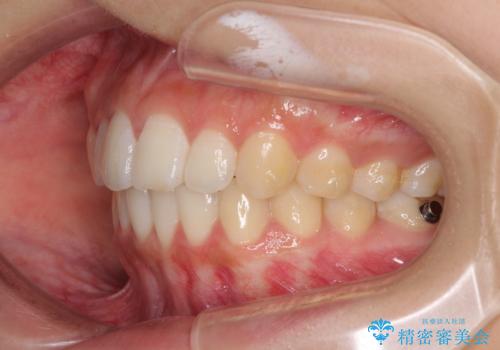

前歯のデコボコと突出感 インビザラインで改善

- 上下前歯のデコボコを気にして来院された患者様です。

インビザラインによる上下歯列の側方拡大と後方移動、IPR(歯と歯の間を削る)にるスペースの獲得により歯列を整えることとしました。

骨格的な左右差があったため、上下の正中を合わせることは困難かと思われましたが、何とか合わせることができました。

一方、骨格の差は改善できないため、奥歯の咬み合わせに物足りなさを感じました。

奥歯の咬み合わせによる不自由はなく、患者様に大変満足していただきました。